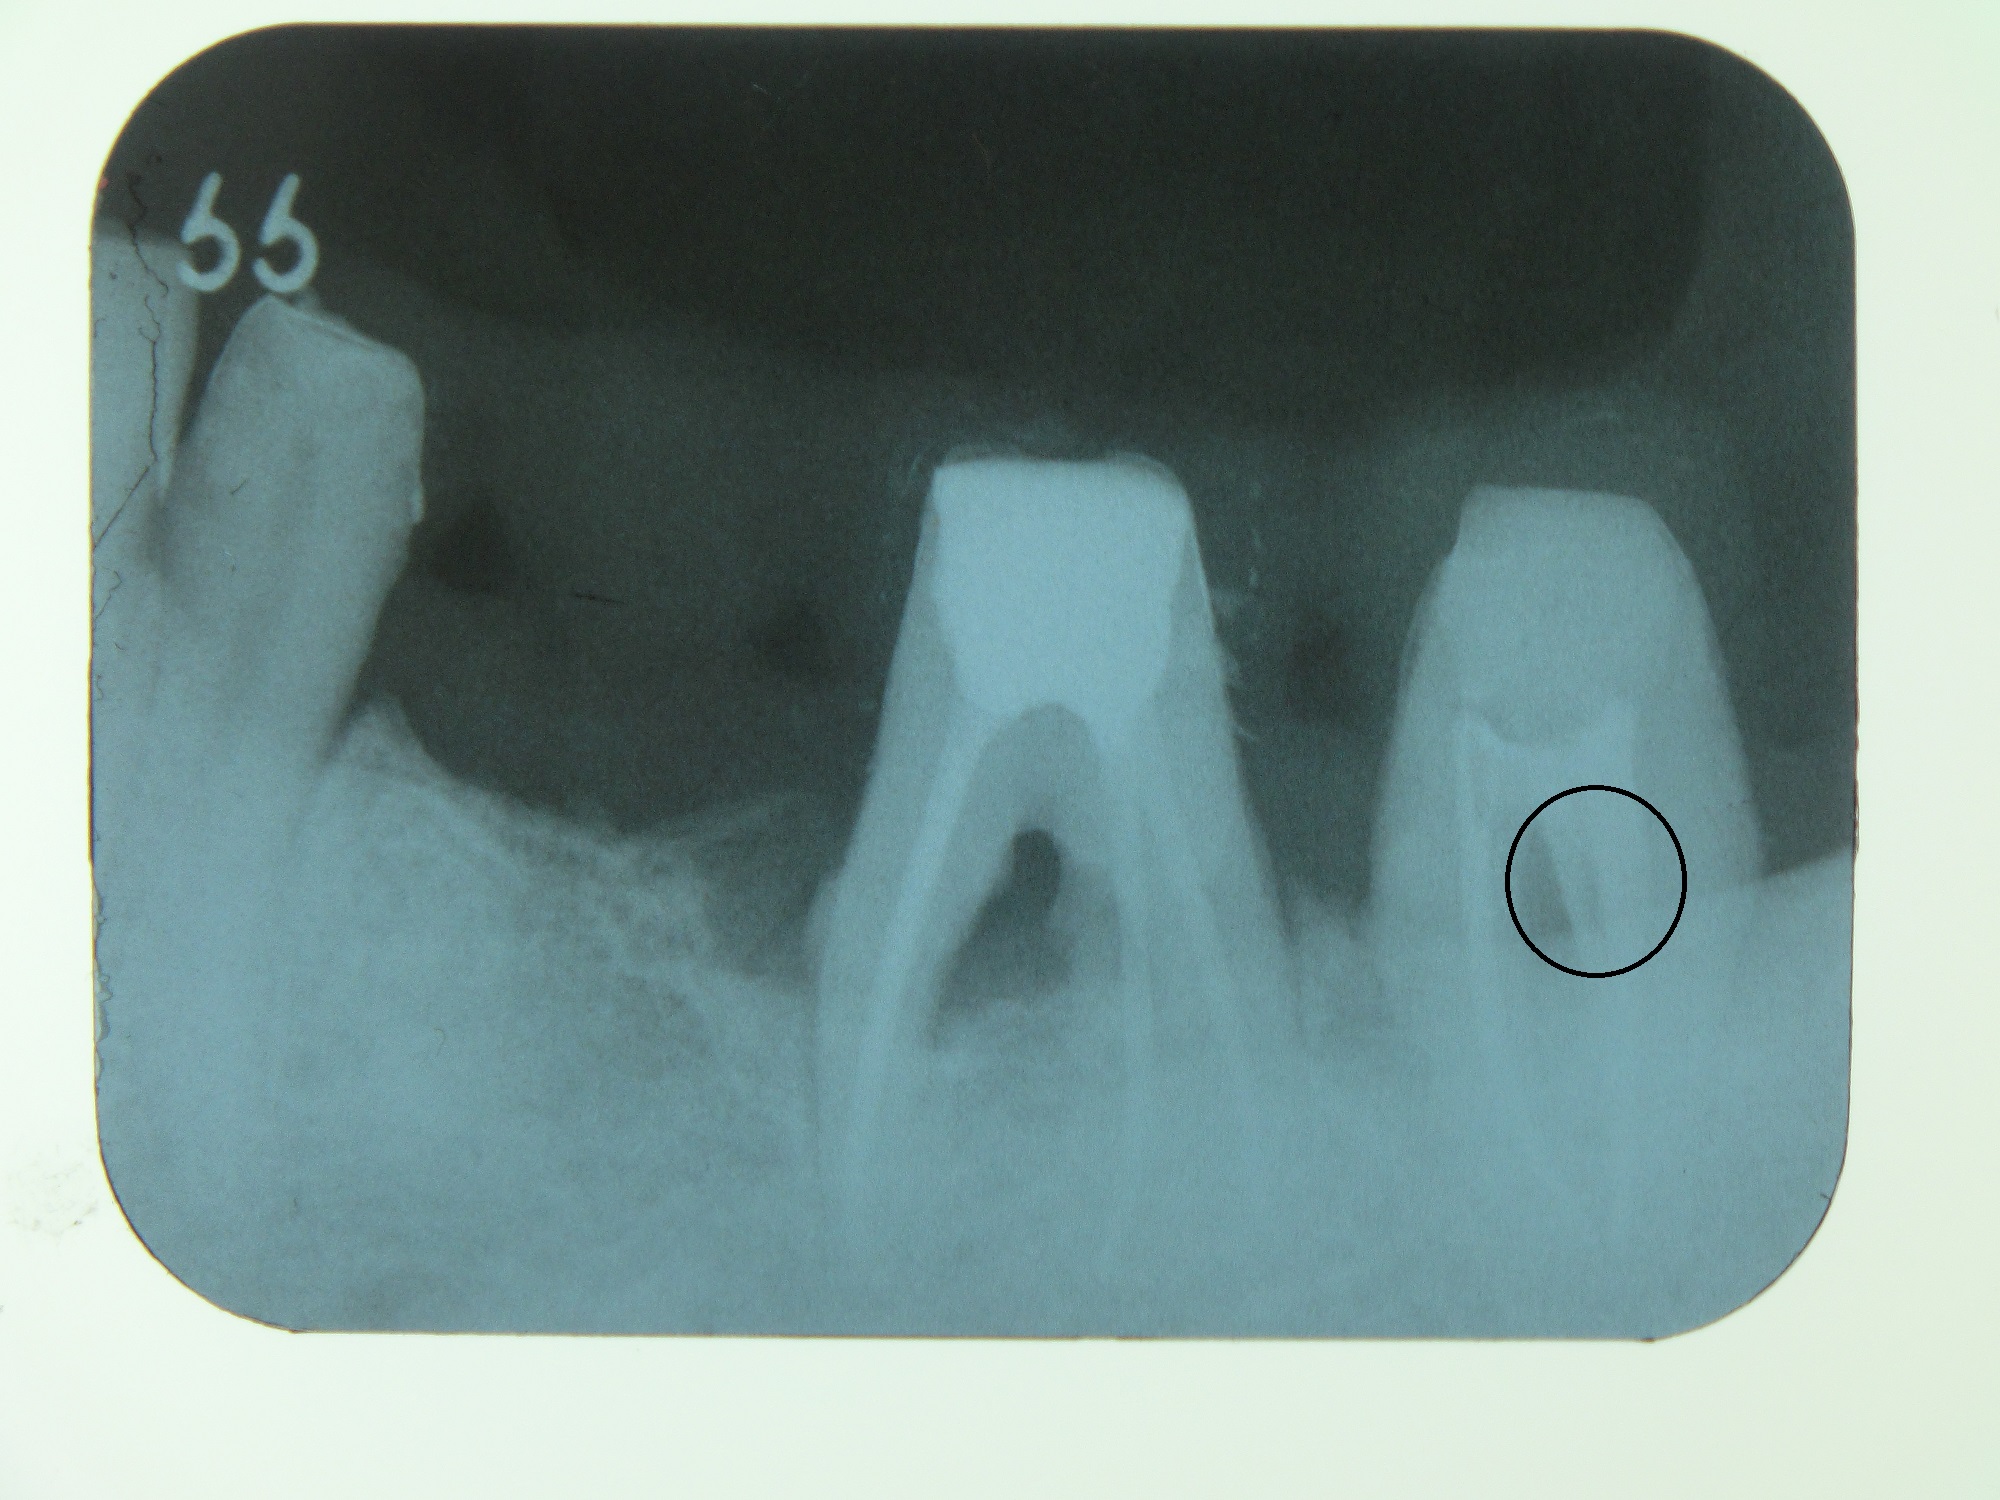

CASE3

以前に根管治療をしたところが再度痛みだしてきたとの事で来院されました。レントゲンなどでしっかり確認してみると、この患者様の根の形態がロート状でした。前回の処置でしっかり根管治療が出来ていなかったことが、再度痛みだしてきたり腫れて来た原因でした。当院で、しっかり根管治療をした後、持続的な殺菌効果を期待してMTAセメントで根管充填しました。